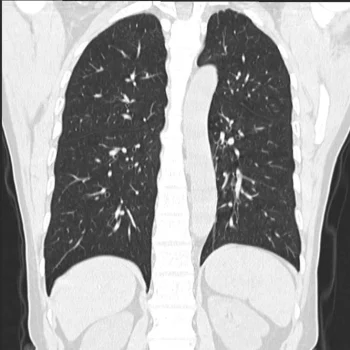

- Das neurovaskuläre System, die kleinen Gefäße der Nierenarterien und der Lungenarterien sind deutlich dargestellt.

• Pneumologie: Lungenrundherdanalyse, Pneumonie und Lungenfunktionsprüfung.